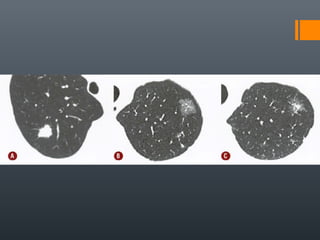

O documento discute vários conceitos radiológicos incluindo consolidação, atelectasia, nódulos, pseudocavidades e padrões intersticiais, fornecendo definições, sinais e diagnósticos diferenciais para cada tópico. Ele também discute a redução da atenuação pulmonar e fornece um link para mais informações.